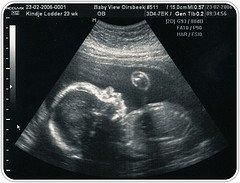

¿Son inocuas las ecografías?

¿Realmente son inocuas las ecografías? Hace tanto que las ecografías se han incorporado a la práctica obstétrica que se asume que no dañan al bebé. Sin embargo hace ya años se comprobó por ejemplo que la exposición a los ultrasonidos aumentaba las posibilidades de que el bebé terminase siendo zurdo (Kieler 2001). Ahora que comienza a aumentar la alarma por el aumento de diagnósticos de autismo algunos investigadores se preguntan si los efectos de las ecografías (calor y vibraciones) en los tejidos cerebrales no tendrán algo que ver. En un artículo de revisión sobre el tema publicado por la revista Midwifery Today en 2006 Carol Rodgers explica: Un reto para los ecógrafos suele ser colocar el trasductor ecográfico sobre la parte de la cabeza del feto que se intenta visualizar. Cuando los fetos se alejan de la fuente de ondas ultrásónicas de alta frecuencia, pueden estar notando vibraciones, calor o ambas cosas. Como alertó la FDA americana en el 2004, "los ultrasonidos son una forma de energía, e incluso se ha comprobado en experimentos de laboratorio como dosis bajas de ultrasonidos pueden producir un efecto físico en el tejido, como las vibraciones discordantes y un aumento en la temperatura" (informe FDA sobre ecografías de 2004) Esto coincide con una investigación hecha en 2001 en la que con un hidrofono en miniatura localizado dentro del utero de una mujer se grabó el sonido que se producia con un ecógrafo dirigido hacia el mismo, el ruido resultó ser "tan alto como un tren entrando en la estación de metro" (Ver recomendaciones FDA o Casadevall, 2018) Un incremento en la temperatura de los tejidos fetales puede parecer poco preocupante, especialmente porque la embarazada ni siquiera lo puede notar, pero los aumentos de temperatura pueden causar daño significativo en el sistema nervioso central del feto en desarrollo según una investigación (Miller 2002) Entre los mamíferos, el aumento de la temperatura materna o fetal se ha asociado con malformaciones en el feto. Un trabajo de revisión extensa de los estudios sobre la hipertermia maternal en una amplia serie de mamiferos halló que "la consecuencia mas frecuente de la hipertermia en todas las especies mamíferas parecen ser los defectos del SNC, y que la muerte celular o el retraso en la proliferación de los neuroblastos (celulas embrionarias que dan lugar a las neuronas) parecen ser la explicación de estos efectos "(Graham, 1998) Sobre hipertermia en tejidos fetales mamíferos ver Ewards, Walsh y Li, 1997

Todo ello nos hace preguntarnos si además de la excesiva medicalización y falsas alarmas que a menudo generan las ecografías no se estará además dañando a los bebés mucho más de lo que se piensa. El artículo de Rodgers (en inglés) incluye toda una serie de referencias a estudios científicos serios sobre el tema y señala que los efectos parecen ser dosis dependiente, es decir, a mayor exposición a ecografías más posible parece ser el efecto dañino. Seguiremos reclamando el derecho de toda mujer embarazada a ser informada con veracidad y rigurosidad sobre los riesgos y beneficios de cualquier procedimiento al que se le ofrezca ser expuesta. Caroline Rodgers Extraido "Preguntas sobre las ecografias prenatales y el alarmante incremento de autismo" Citado en Midwifery Today, Issue 80 Un desafío al que se enfrentan los operadores de ultrasonido (equipos para ecografía) es el de mantener el transductor colocado sobre la zona del feto que el operador está tratando de visualizar. Cuando el feto se mueve fuera de la corriente de ondas sonoras de alta frecuencia, puede que lo hagan por oyen vibraciones, calor o ambos. La FDA alertó en 2004 de que “estudios de laboratorio han demostrado que los ultrasonidos son una forma de energía incluso a bajos niveles, que puede producir efectos físicos en los tejidos, tales como vibraciones de sacudida e incremento de temperatura.” (9) L descrito aquí concuerda con las investigaciones llevadas a cabo en 2001, en las que un transductor de ultrasonidos se dirigía directamente a un hidrófono colocado en el útero de una mujer, y el cual recogió un sonido “tan fuerte como el de un tren subterráneo entrando en una estación". (10) Un incremento de temperatura del tejido fetal puede no parecer alarmante- sobre todo teniendo en cuenta que la madre no puede sentirlo-, pero pueden causar daños significativos en el sistema nervioso central de un feto en desarrollo, según se indica en algunas investigaciones.(11) En diferentes especies de mamíferos, se ha demostrado que una temperatura elevada tanto en el cuerpo de la madre como en el feto, resultan en defectos de nacimiento de la prole. (12) Una intensiva revisión de la literatura científica relacionada con hipertermia maternal en una variedad de mamíferos muestra que “los defectos del sistema nervioso central (SNC) parecen ser la consecuencia más frecuente de la hipertermia en todas las especies, y la explicación más importante de estos efectos, es la muerte celular o el retraso en la proliferación de neuroblastos (células embrionarias que dan lugar a las células nerviosas)” (13) ~ Caroline Rodgers Extraido "Questions About Prenatal Ultrasound and the Alarming Increase in Autism" Citado en Midwifery Today, Issue 80 Read the full article: https://midwiferytoday.com/mt-articles/questions-prenatal-ultrasound/ Las mujeres estadounidenses tienen una probabilidad el doble de alta de recibir ultrasonidos, que hace 10 años. De acuerdo con la investigación publicada recientemente en la revista científica Medical Care, las mujeres embarazadas en los EEUU, tienen una probabilidad más alta de recibir exámenes con ultrasonido prenatales de forma repetida, que hace 10 años. En un estudio llevado a cabo por el Departamento de Medicina Preventiva de la Universidad Northwestern, los investigadores analizaron la cantidad media de ecografías prenatales por embarazo y el porcentaje de visitas prenatales que incluían un examen de ultrasonido, registrados en los hospitales a través de los formularios completados en los periodos de 1995 a 2000, y de 2005 a 2006, dentro del Informe Nacional de asistencia médica ambulatoria en hospitales. Los resultados mostraron que, para mujeres con embarazos de bajo y alto riesgo, la media de ecografías por embarazo se incremento entre 1,3 y 2,1, y entre 2,2 y 4,2, respectivamente. “En un análisis ajustado, la probabilidad de que a una mujer se le practicara una ecografía entre 2005 y 2006, era el doble de la probabilidad de que se le realizara una en una visita entre 1995 y 1997”, afirmaban los investigadores, añadiendo que en el caso de las mujeres con embarazos de alto riesgo, la probabilidad de que se les realizara una ecografía en una visita prenatal era doble que si eran de bajo riesgo. ~ Siddique, Juned, et al., 2009. Med